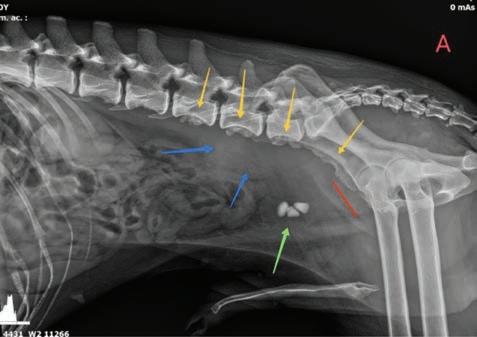

Se realizaron radiografías torácicas y en la proyección lateral derecha se observó, craneal a la silueta cardiaca, una opacidad tejido blando mal definida que producía efecto silueta positivo con esta. La tráquea se visualizó desplazada dorsalmente y el atrio izquierdo aumentado de tamaño. El parénquima pulmonar mostraba un aumento de opacidad en su área caudodorsal, compatible con un patrón pulmonar intersticial no estructurado difuso, el cual se consideró normal debido a que la radiografía fue tomada en fase espiratoria inicial

163

y a la condición corporal del paciente. En la proyección ventrodorsal, el mediastino craneal se observó en el límite superior de tamaño, presentándose un tamaño dos veces superior a la anchura de la vértebra torácica (Fig. 1). Este cambio es compatible con una imagen artefactual secundaria a la leve rotación que presenta la radiografía y a la condición corporal del paciente. El diagnóstico radiológico más probable fue una masa mediastínica craneoventral y cardiomegalia izquierda. En la ecocardiografía transtorácica se confirmó el diagnóstico de enfermedad degenerativa de la válvula

Figura 1. Radiografías torácicas en proyección lateral derecha (A) y ventrodorsal (B) donde se visualiza el área de opacidad de tejido blando craneal a la silueta cardíaca (flechas blancas). En la proyección ventrodorsal se visualiza el mediastino craneal que se presenta en el límite superior de grosor (flechas rojas).

En el registro electrocardiográfico se observó un ritmo irregular en el que alternaron latidos sinusales y prematuros. La morfología del QRS de los latidos prematuros fue de complejos estrechos (<70 ms) y muy similares al latido sinusal precedente. La cadencia del ritmo era de dos complejos estrechos con intervalo RR estable. Este patrón de QRS estrecho-QRS estrechopausa se repitió de manera continuada y fue independiente de las fases del ciclo respiratorio. El primer QRS venía precedido de una onda P sinusal y el complejo prematuro de una P’ con diferente morfología, lo que se interpretó como actividad atrial ectópica. La realización de un ECG de 6 derivaciones permitió analizar la morfología de la onda P’, que fue positiva en derivaciones I, II, III y aVF, y negativa en derivaciones aVR y aVL (Fig. 3). El diagnóstico electrocardiográfico fue de complejos prematuros atriales frecuentes (ritmo bigémino atrial).

Figura 3. Electrocardiograma de 6 derivadas. Complejos prematuros atriales frecuentes (bigémino). Onda P’ positiva en derivaciones I, II, III y aVF, y negativa en derivaciones aVR y aVL.